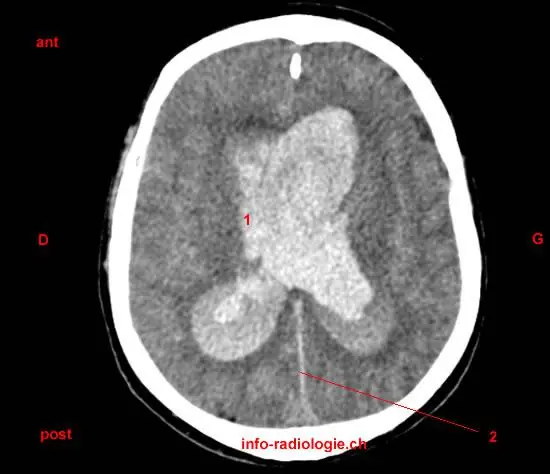

Hémorragie sous arachnoidienne hémorragie sous arachnoidienne anévrisme Anévrisme anevrisme Anevrisme anévrysme Anévrysme

trauma cranien Trauma cranien Traumatisme cranien traumatisme cranien grave